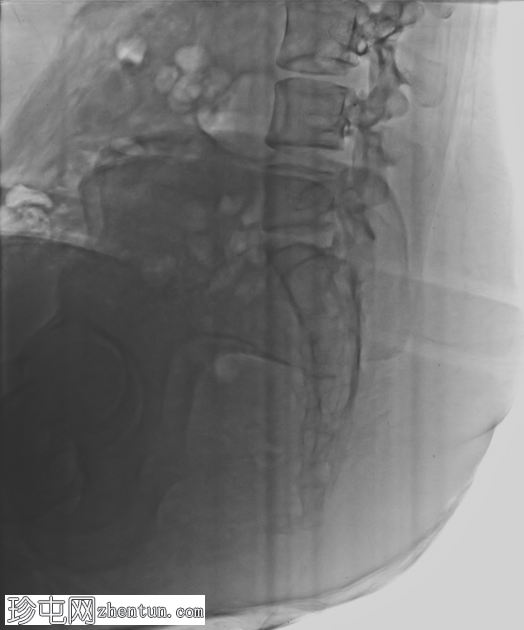

侧位片

远端尾骨节段相对于正常排列呈前倾角增大。未见急性骨折线或脱位。未见局灶性溶骨性或硬化

性病

变,提示无

肿瘤

。

侧位尾骨X线片是评估排列情况并排除骨折/脱位的首选

影像

前倾角增大但无骨折支持机械性尾骨痛的诊断。